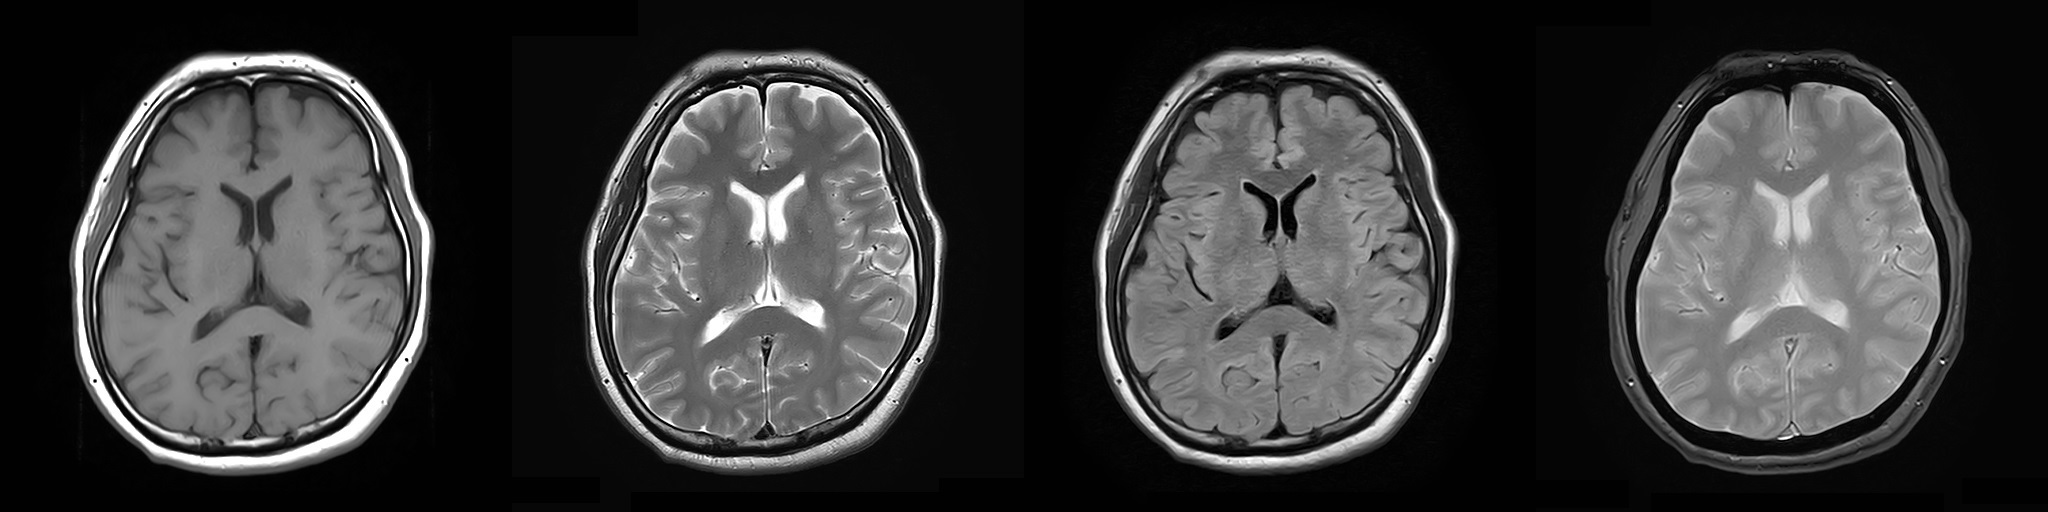

MRI(磁気共鳴画像)装置

2022年2月にMRI装置を更新いたしました。

1.5TのMIR装置(富士フイルムヘルスケア株式会社製「MRイメージング装置 ECHELON Smart」)を導入し、以前よりも短い時間で高画質の撮像が可能になりました。

MRIは体内の断面像を縦、横、ナナメから人体に悪影響を与えずに見ることが出来る装置です。わずかな病変も見逃さない鮮明な画像は腫瘍などの早期発見や健診に威力を発揮します。薬品を全く用いずに血管撮影等が出来るので、患者さんは動かずに横になるだけで苦 痛なく精密検査が受けられます。

T1強調像 / T2強調像 / FLAIR像 / T2*強調像